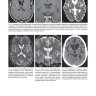

Книга построена по принципу руководства по дифференциальной диагностике, в основе ее рубрификации лежат особенности диагностических изображений. Иллюстрации размещены на разворотах слева, справа дается емкое описание наблюдаемой патологии и список для дифференциальной диагностики с указанием страниц, на которых описаны дифференцируемые состояния. В руководстве приведено более 1500 изображений (в основном компьютерных и магнитно-резонансных томограмм) головного мозга, наблюдаемых при более чем 200 заболеваниях. Книга начинается с описания картины двусторонних симметричных поражений и срединных дефектов, так как их легче всего спутать друг с другом, особенно если читатель имеет относительно небольшой опыт.

Примеры страниц из книги "КТ- и MPT-визуализация головного мозга. Подход на основе изображений" - Румболдт Зоран